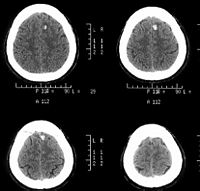

双颞叶脑挫裂伤

CT扫描

对脑挫裂伤与脑震荡可以作出明确的鉴别诊断,并能清楚地显示脑挫裂伤的部位、程度和有无继发损害,如出血和水肿情况。同时,可根据脑室和脑池的大小、形态和移位的情况间接估计颅内压的高低。尤为重要的是,对一些不典型的病例,可以通过定期CT扫描,动态地观察脑水肿的演变或迟发性血肿的发生。近年来,在有此设备的医院CT已作为急性头伤的常规检查,因为单靠伤史和查体难以作出超早期诊断。Stein等(1990)指出在GCS13~15危害较小的轻型头

伤中,首次CT的阳性发现率竟占18%,并有5%需行手术治疗,强调早期CT检查的必要性。